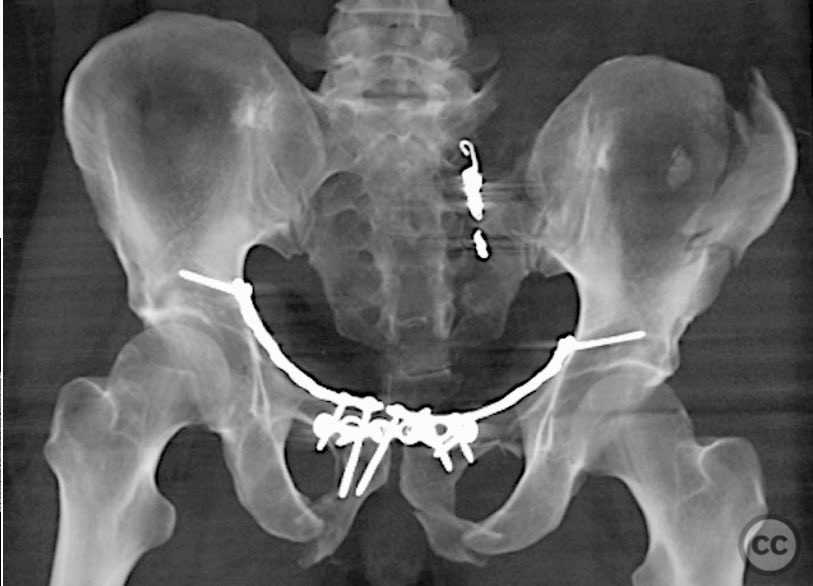

Clinical and radiological findings:  A 42-year-old male sustained a high-energy motor vehicle accident resulting in an unstable pelvic ring injury (AO/OTA 61-C1.3) with hemodynamic instability and associated intraperitoneal bladder rupture. Initial computed tomography demonstrated a complex anterior pelvic ring disruption and a posterior sacral fracture with contrast extravasation and blood within the fracture site. The patient was hemodynamically unstable on presentation.

Planning remarks:  The preoperative plan included multidisciplinary management with urology for bladder repair, followed by open reduction and internal fixation of the anterior pelvic ring via an anterior approach. Subsequent posterior pelvic stabilization was planned after initial resuscitation and anterior fixation, utilizing a posterior approach for direct sacral reduction and percutaneous iliosacral screw fixation.

The case was notable for initial successful multidisciplinary management of both hemodynamic instability and intraperitoneal bladder injury, allowing for staged surgical intervention. Despite accurate anterior pelvic reduction and fixation, postoperative imaging revealed worsening posterior sacral displacement, necessitating subsequent posterior open reduction. The use of a tenaculum clamp facilitated direct anatomical reduction of the sacral fracture prior to iliosacral screw fixation. The presence of an embolic coil from prior angioembolization did not impede surgical access or hardware placement. This case demonstrates that initial anterior pelvic ORIF does not complicate or preclude subsequent routine posterior pelvic ORIF in complex unstable ring injuries.

Orthopaedic implants used:   Anterior pelvic reconstruction plate, iliosacral cannulated screws, tenaculum reduction clamp